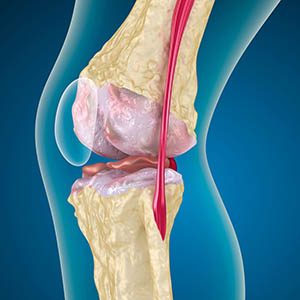

При артрозе хрящ, выстилающий края костей, истирается или полностью отсутствует. Поврежденная ткань не является источником боли, поскольку не имеет рецепторов. Воспаление в близлежащих структурах вызывает характерные симптомы.

Организм продолжает регенерацию поврежденных тканей, но хрящ нарастает неравномерно. В результате образуются неровности, травмирующие другие элементы сустава. Природа остеофитов поясняется компенсацией гладкого суставного хряща. Другая версия свидетельствуют о том, что разрастание «шпор» связано с попыткой стабилизировать сустав медиально или латерально из-за ослабления мышц.